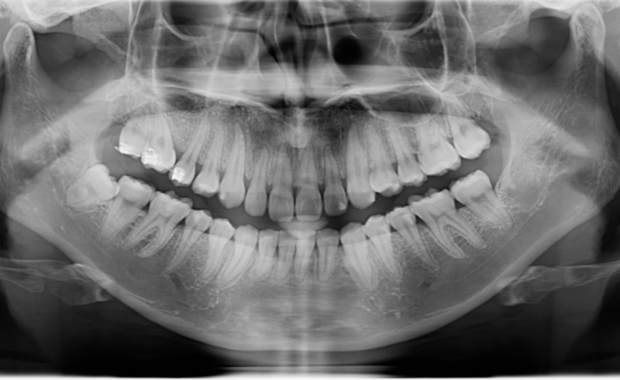

パノラマレントゲン

顎全体から歯、顎関節、上顎洞(鼻の奥の空洞)までを一枚の画像に収めることができるレントゲンです。見た目ではわからない、虫歯や歯周病の進行具合、親知らずの位置、神経の通り道、歯の根っこの状態などを確認し、正確な治療計画を立てるために必要不可欠ですので、当院では全ての患者様にご案内いたします。